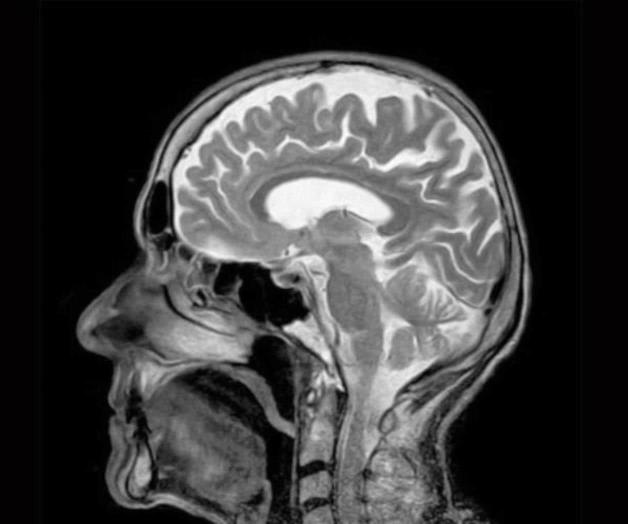

A través de un nuevo método de análisis cerebral expertos observaron que el cerebro funciona como un todo unificado y no por regiones aisladas como se llegó a creer. Investigadores de la Universidad de Duke confirmaron que el cerebro funciona como una red integrada e interdependiente, a través del uso de un método de medición, por el cual emplearon imágenes de resonancia magnética.